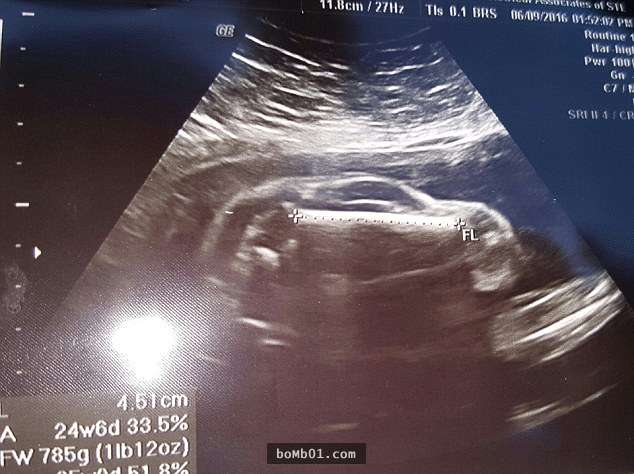

第一次看到寶寶的超音波照片,準父母們一定會很激動。但不久前,國外一名網友帶妻子去做檢查時,卻看到了驚人的一幕。超音波檢查照片中顯示的不是胎兒的形狀,反而看起來像一台跑車。他覺得非常吃驚,將這張照片上傳到網路上與大家分享,很快就有490多人留言回應。

▼這張超聲波照片看起來很像跑車,就連車窗、車輪都看得很清楚。

▼網友們紛紛表示,「這絕對會引發中年危機」。